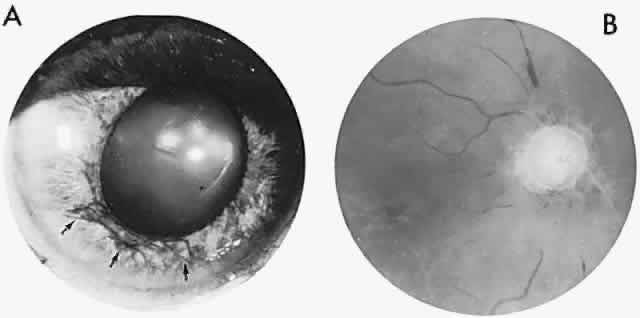

In contrast to transient symptoms and signs of retinal microembolic episodes, a condition of chronic ocular hypoxia (ocular ischemic syndrome) occurs less frequently, resulting from diffuse vascular occlusive disease of the aortic arch or common carotid artery. Acute or chronic occlusion with insufficient collateralization produces an ischemic pseudo-inflammatory uveitis, which variably includes an injected painful globe, corneal edema, aqueous flare and cells, a mid-dilated fixed pupil, rubeosis and iris atrophy, rapidly advancing cataract, either hypotony or elevated intraocular pressure (“neovascular glaucoma”), retinal microaneurysms and new vessel formation, posterior pole and mid-peripheral blot hemorrhages, macular edema, venous dilation and “sausaging,” cytoid infarcts (cotton-wool spots) of the nerve fiber layer, and arterial occlusions (Fig. 7; see Table 4). The hypoxemic fundus changes constitute a picture of venous stasis (low-pressure) retinopathy, perhaps the commonest ocular sign of chronic carotid obstruction.

Fig. 7. Ocular hypoxia with subacute carotid occlusion. The patient complained of a painful red eye. A. Anterior segment shows an irregular, fixed pupil and iris rubeosis (arrows). B. Fundus demonstrates combined retinochoroidal infarction with acute excavation of the optic disc. Arteriography revealed right internal carotid occlusion.